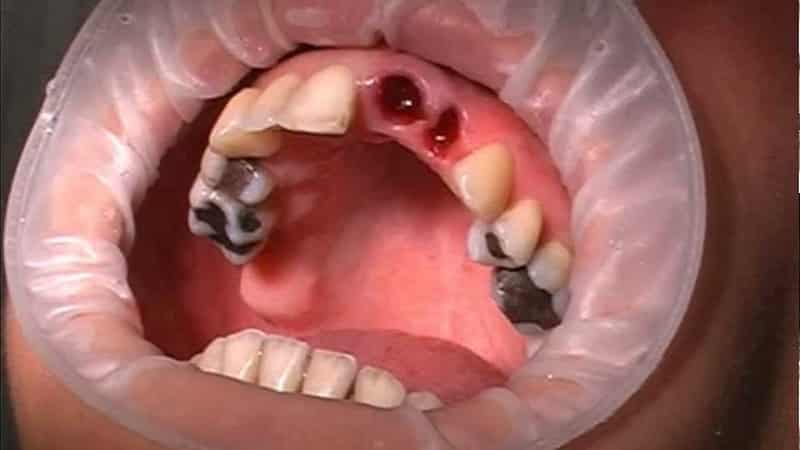

Неприятные последствия могут возникнуть в следующих случаях:

- зуб сильно болел во время экстирпации;

- на корне образовалась киста, которую пришлось удалять из кости;

- в процессе операции зуб сломался на несколько частей, которые врач извлекал частично;

- общая гигиеническая ситуация в ротовой полости оставляет желать лучшего: на зубах много налета, образовались зубные камни;

- во время процедуры были выявлены хронические заболевания ротовой полости и ЛОР-органов;

- заболевания пародонта находились в остром состоянии;

- врач не следовал установленным принципам операции и некачественно обработал рану;

- имели место хронические заболевания соседних зубов.

Осложнения после операции по экстирпации могут развиваться довольно быстро. Первые клинические проявления могут появиться уже к вечеру после процедуры. Далее мы рассмотрим наиболее распространенные осложнения, возникающие после экстирпации.